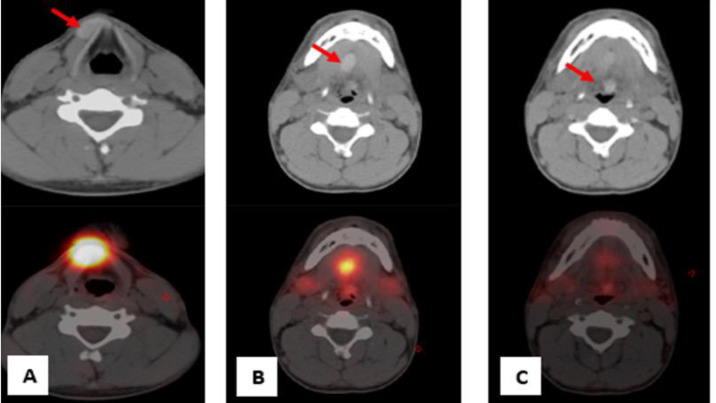

Ectopic thyroid tissue is a rare congenital anomaly, with the presence of three simultaneous ectopic foci being exceedingly rare. We describe a case of a totally asymptomatic 26-year-old male discovered to have triple ectopic thyroid following incidental elevated thyroid-stimulating hormone (TSH) levels. Subsequent ultrasonography of the neck showed an absent thyroid gland in its conventional location. A Technetium-99m pertechnetate (Tc-99m) thyroid scan showed three distinct foci of radiotracer uptake in the upper cervical, lingual, and sublingual regions, corresponding to triple ectopic thyroid. An extensive review of the literature was conducted to provide a broader understanding and deeper insights into this uncommon condition. This case underscores the pivotal role of Technetium-99m thyroid scanning in diagnosing triple ectopic thyroid, particularly in instances where the orthotopic thyroid gland is absent. A comprehensive understanding of this rare entity is indispensable for radiologists and clinicians, enabling accurate diagnosis and informed decision-making regarding the appropriate therapeutic strategies.